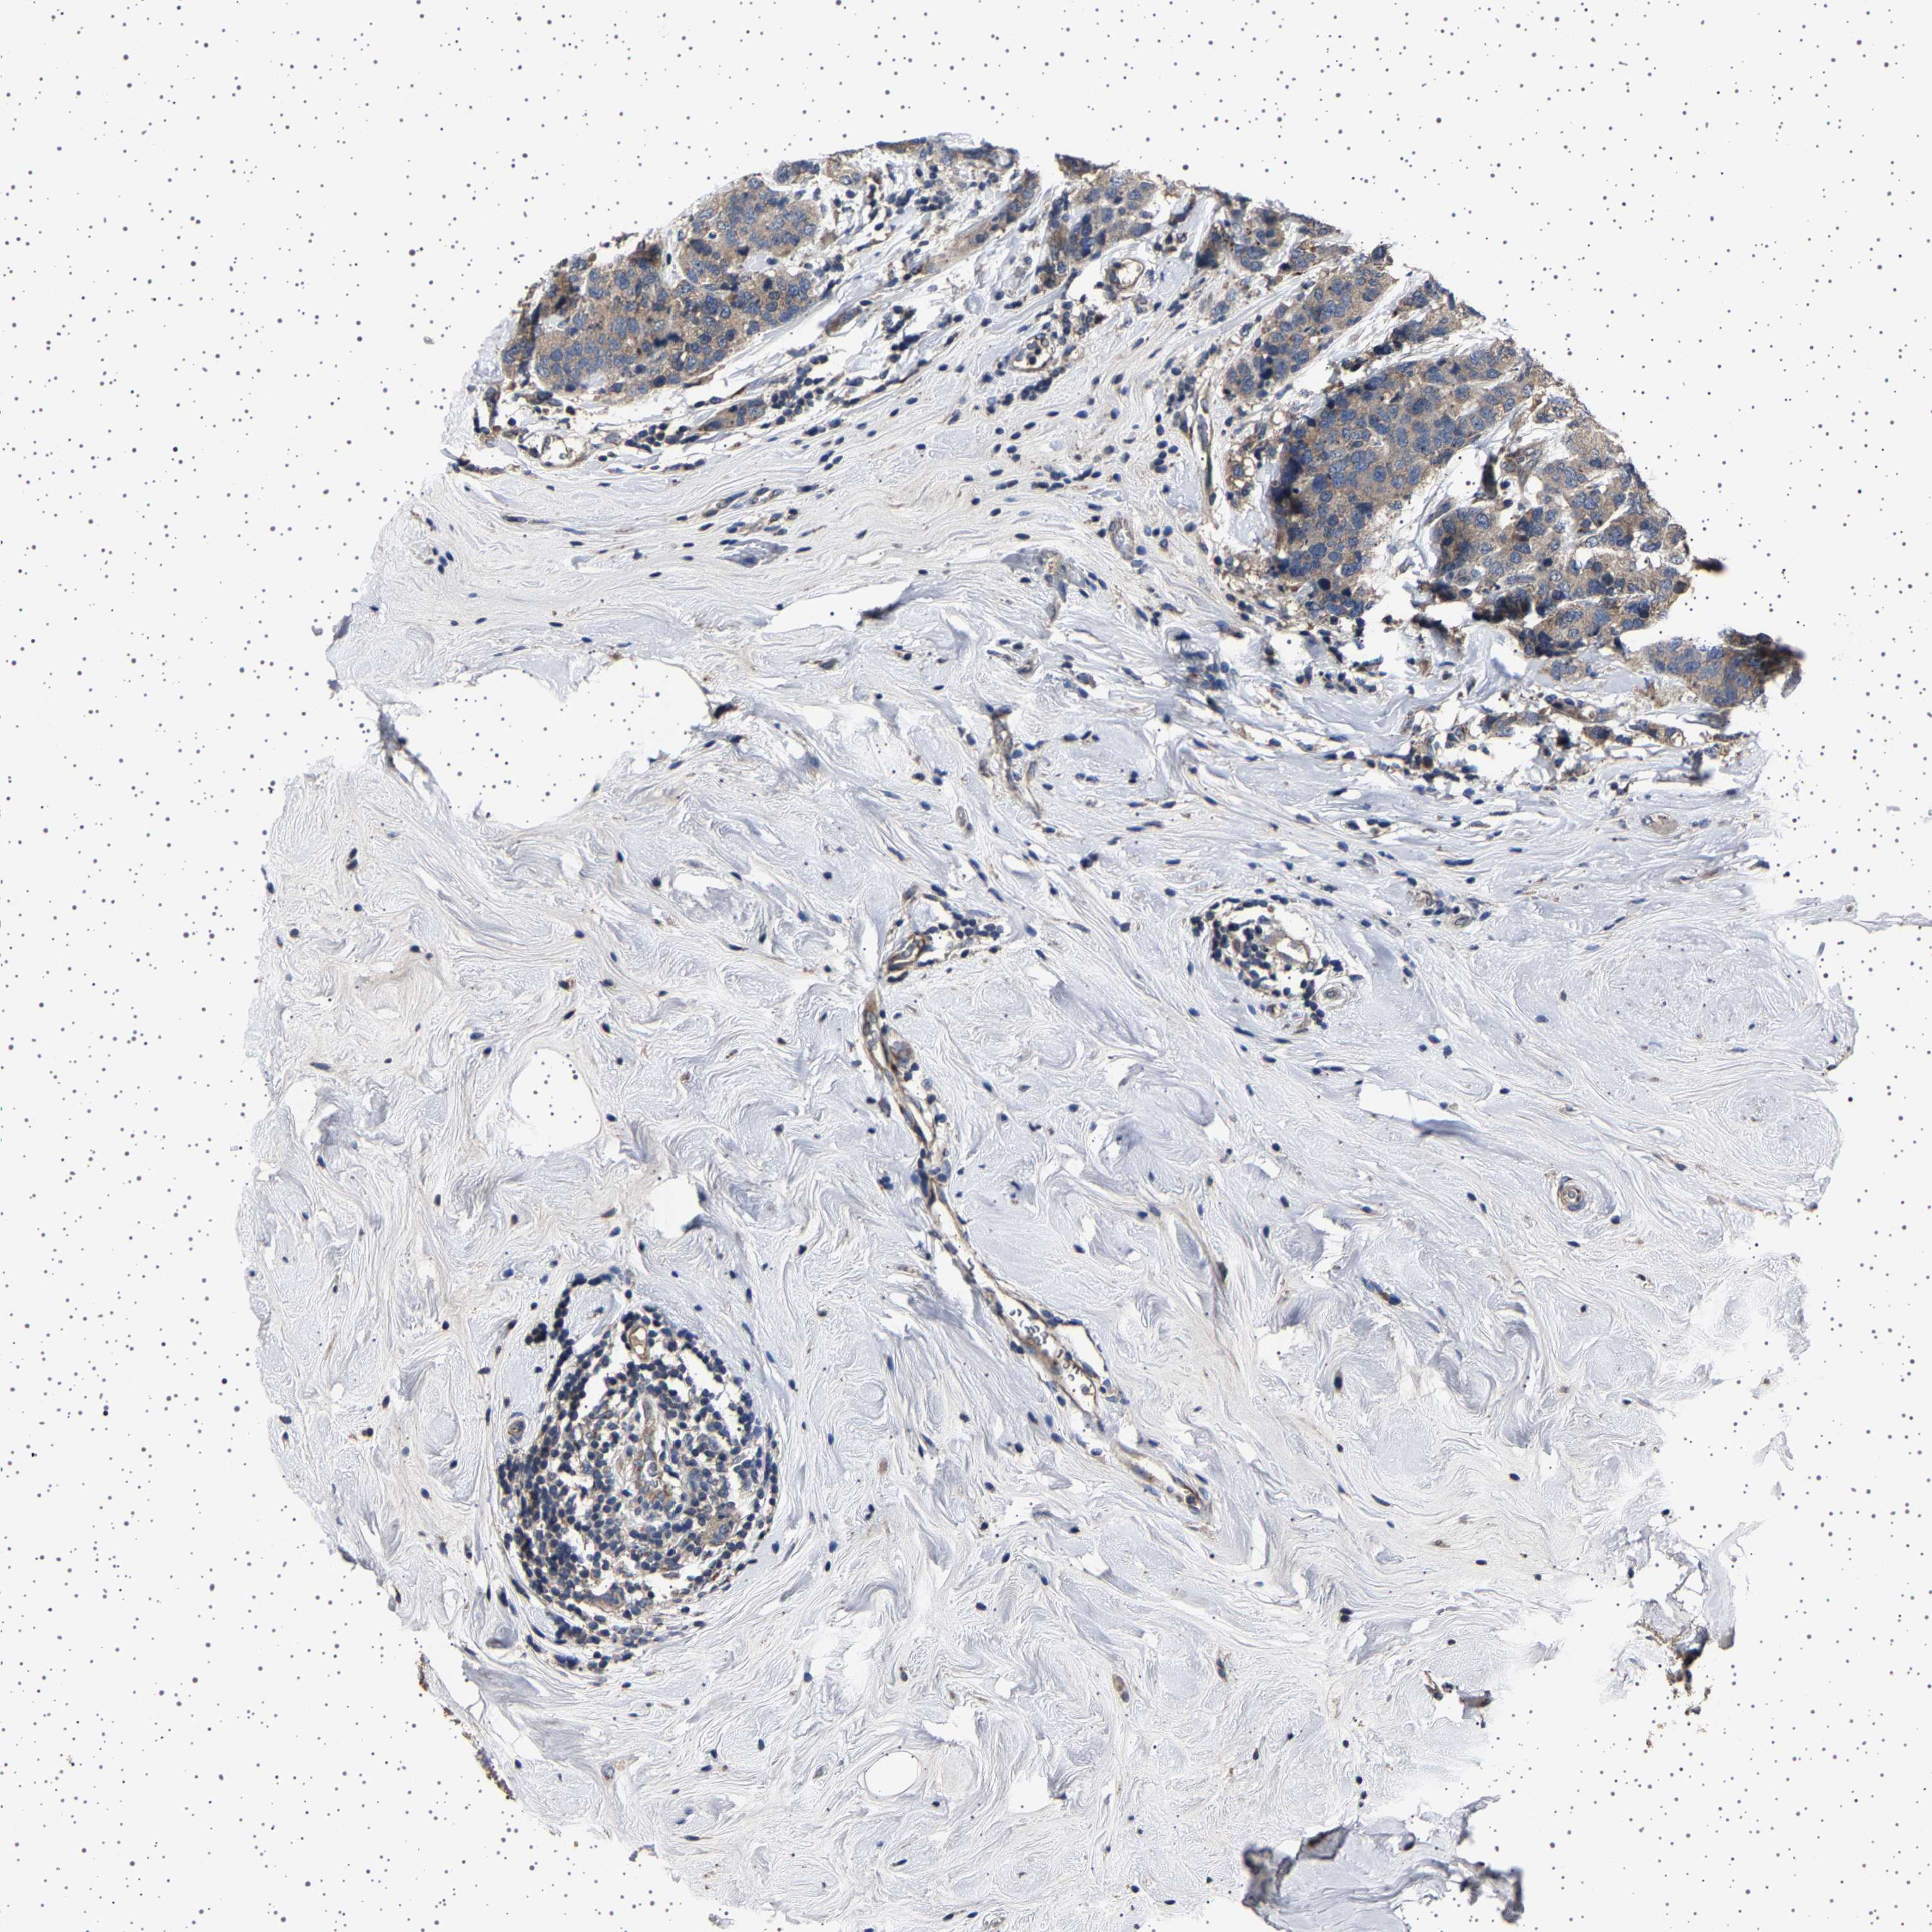

CANCER BREAST CANCER Show tissue menu

BRCA TCGA BRCA VALIDATION PROTEIN EXPRESSION